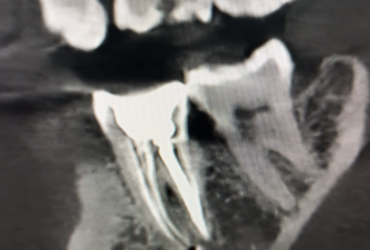

Galería

Algunos de nuestros tratamientos de endodoncia que permiten salvar piezas dentales, eliminar infecciones y devolver la salud y funcionalidad a tu sonrisa.